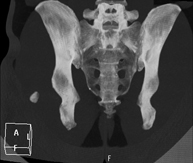

- TC Pelvis

Prueba diagnóstica que consiste en obtener imágenes bi y tridimensionales de la pelvis de alta definición anatómica (estructuras óseas, estructuras vasculares, vejiga, útero y ovarios, próstata y vesículas seminales, uréteres, etc.) mediante el empleo de un equipo de TC (Tomografía Computarizada). La mayoría de estudios requieren el empleo de contraste yodado.